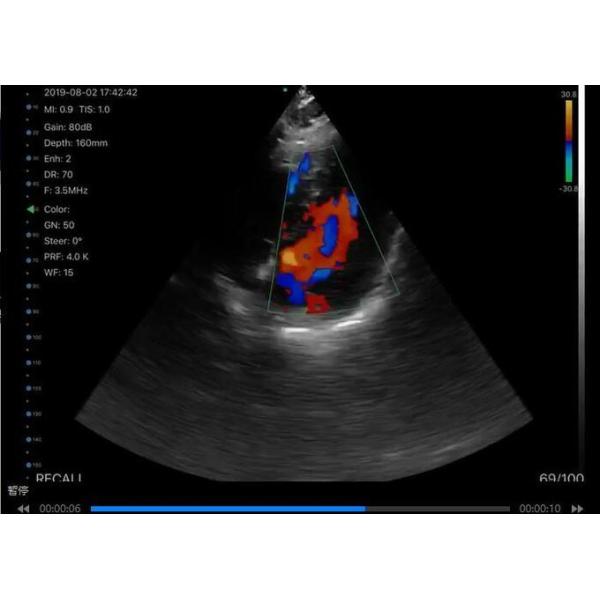

Display Mode : B,BM,Color,PDI,PW

Color Doppler Sonography Color Doppler Ultrasound Scanner With Built-in WiFi Signal

Wireless Charging 2.5MHz~10MHz Freq

| Type | Linear/convex/cardiac | Imaging mode | B,BM,Color,PDI,PW |

| Frequency | Convex:3.5/5Mhz Linear:7.5/10MHz Cardiac:2.5/5Mhz | Depth | Convex:90~305mm Linear:20~80mm Cardiac:90~160mm |

B+PW: Velocity, Heart Rate (2), S/D, Depth | Applications: -Abdomen -Obstetrics/ Gynecology -Cardiac -Kidney -Urology -Breast -Thyroid -MSK -Vascular -Pediatrics -Carotid -Small Parts |

| 6 | Suitable for more than 20 clinical applications of systemic examination | liver, gallbladder, spleen, kidney, bladder, obstetrics and gynecology, blood vessels, thyroid, breast, nerve, musculoskeletal, small organs, hip bone, Cardiac, etc. |

Color Doppler Sonography Color Doppler Ultrasound Scanner With Built-in WiFi Signal Wireless Charging 2.5MHz~10MHz Freq Images |